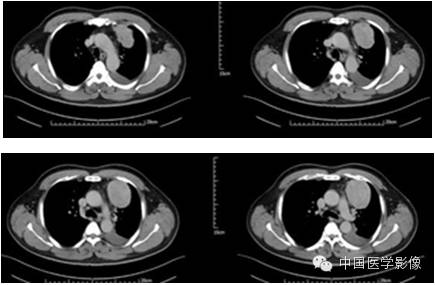

病例1【病史】

患者男,50岁。

患者因“突发胸痛4余天”入院。患者无发热、盗汗,无声音嘶哑,无咳痰,无面部及双下肢肿胀。门诊以“左前上纵膈肿瘤”收入院。患者自发病以来,饮食睡眠可,大小便正常,体重较前无明显减轻。既往高血压病史1年,否认其他传染病史。

专科查体:胸廓对称,双侧呼吸动度均等,胸壁无明显压痛及肿块,双侧语颤正常,双肺叩清音,左下肺呼吸音低,右肺呼吸音可,双肺未闻及干湿啰音。

入院诊断:左前上纵膈肿瘤:畸胎瘤?

【影像资料】

平扫